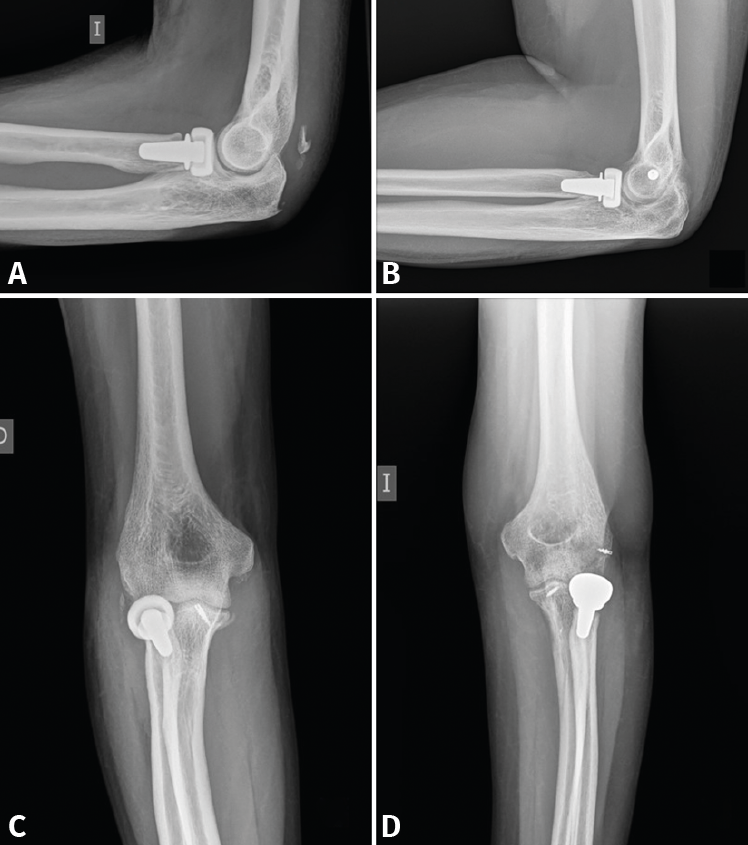

- Sustitución (prótesis de la cabeza del radio): de elección cuando la síntesis no sea posible, cuando no se consiga una fijación estable o en el caso de lesiones complejas con inestabilidad(17,18). Existen varios tipos de prótesis en el mercado, la más usada es una prótesis modular, metálica, no cementada. Hay que evitar 2 errores básicos en la técnica. El primero, no sobredimensionar el tamaño, es decir, implantar un diámetro igual o menor que el diámetro menor de la cabeza natural (recordemos que la cabeza del radio es ovalada)(19). Y el segundo, realizar el corte adecuado y sin excesiva presión de contacto sobre el cóndilo humeral, pues eso supondría una erosión del cartílago y la consecuente artrosis secundaria con dolor crónico(20,21). Es útil el uso de un intensificador de imágenes para comprobar que no sobrepasa la altura de la coronoides y que la articulación es congruente (Figura 6).

Figura 6. Varios ejemplos de fracturas tratadas con prótesis de la cabeza del radio (A), con reinserción del ligamento colateral lateral (LCL) (B), de la cápsula anterior por fractura de coronoides de tipo I de Regan (C) y con reinserción de ambos (D).